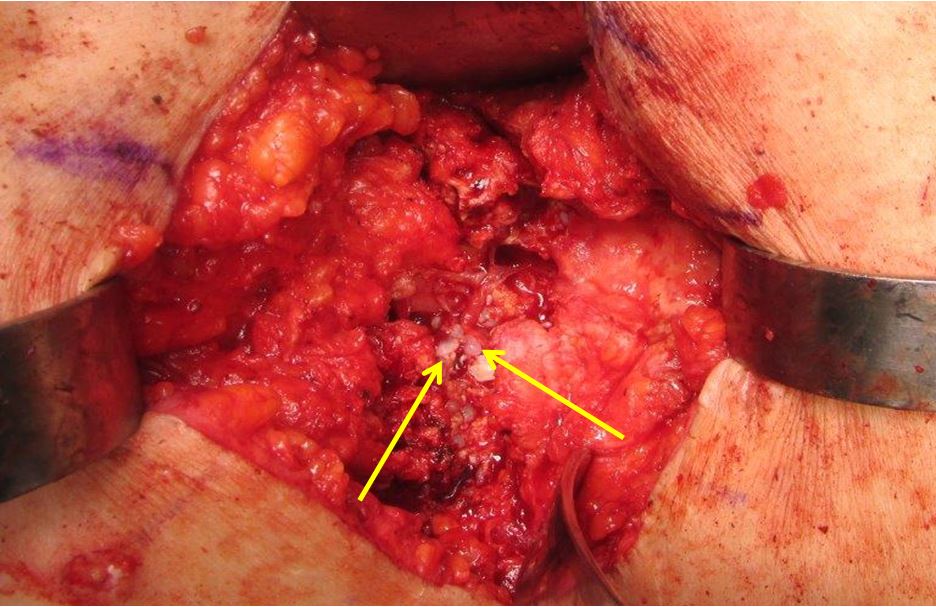

Fig. 6: Case 1 - Histopathologic slides (H&E stain) demonstrating hooks and scolices consistent with Echinococcus multilocularis. A. Hooklet (100x magnification). B. Hydatid cyst with black-staining structures suggestive of degenerating hooklets. C. Zoomed detail of cyst wall. D. Degenerating hydatid cyst and hooklets..jpg)